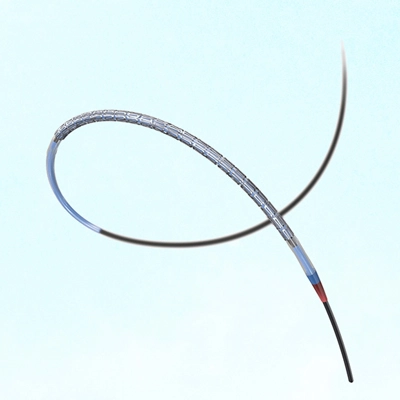

A stent is an expandable metal mesh tube to treat narrowed or blocked blood vessels, including coronary arteries. It is designed to hold open the artery walls and improve blood flow to the heart. The stent gets placed in the blocked artery during a stent procedure or coronary angioplasty, an interventional procedure used to treat coronary artery disease.

The stent procedure in the heart, known as percutaneous coronary intervention (PCI), is a minimally invasive procedure to treat narrowed or blocked coronary arteries effectively. During the procedure, a thin catheter gets inserted into an artery through the groin or wrist and guided to the blocked artery in the heart. A small balloon at the catheter’s tip gets inflated to help widen the artery and improve blood flow.